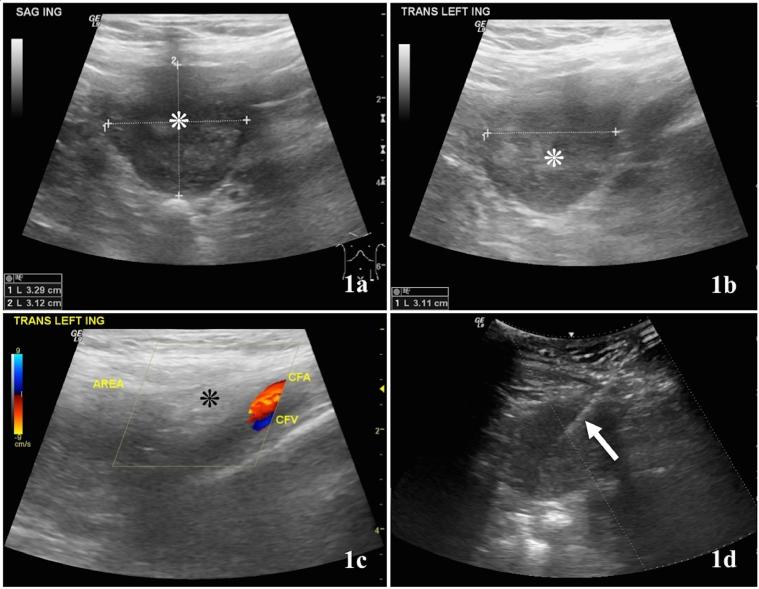

Uterine leiomyomas are one of the most common tumors affecting reproductive-age women. Leiomyomas can present as an intrauterine mass or rarely as an extrauterine tumor. Depending on its location, the diagnosis of extrauterine leiomyoma can be challenging, and multiple imaging modalities may be needed for correct identification and differentiation from malignant entities. We report the case of a 48-year-old-postmenopausal female who presented with a painful left inguinal mass, which was clinically diagnosed as inguinal hernia. Ultrasound, computed tomography, magnetic resonance imaging, and percutaneous biopsy were used to characterize the mass. Surgical resection and histopathological analysis revealed the mass to be a parasitic leiomyoma, a very rare cause of inguinal hernia, especially in a postmenopausal woman.

子宫平滑肌瘤是影响育龄女性的最常见肿瘤之一。平滑肌瘤可表现为子宫内肿物,极少情况下表现为子宫外肿瘤。根据其位置,子宫外平滑肌瘤的诊断可能具有挑战性,可能需要多种成像方式来正确识别并与恶性病变相鉴别。我们报告一例48岁绝经后女性病例,该患者出现左侧腹股沟肿物伴疼痛,临床诊断为腹股沟疝。通过超声、计算机断层扫描、磁共振成像及经皮活检对肿物进行特征性描述。手术切除及组织病理学分析显示该肿物为寄生性平滑肌瘤,这是腹股沟疝非常罕见的病因,尤其在绝经后女性中。